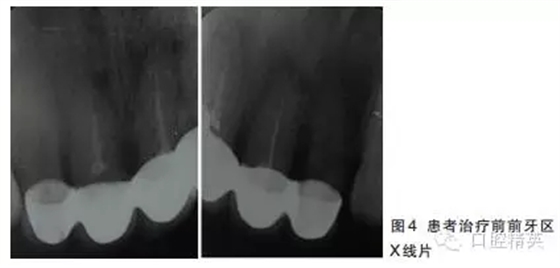

12~22烤瓷聯(lián)冠修復(fù),冠邊緣不密合,齦緣外形不協(xié)調(diào),牙齦紅腫,22烤瓷冠崩瓷。根管治療不完善,牙齦根尖部位有瘺管,X線影像顯示11、21根尖有陰影。

董艷梅教授:修復(fù)前如有以下情況,應(yīng)考慮進(jìn)行根管再治療:①X線片顯示前次根管治療不完善;②X線片顯示患牙根尖周新增病變或根尖周病變范圍擴(kuò)大或未見縮小;③患牙在前次根管治療后長(zhǎng)期有癥狀或臨床體征。